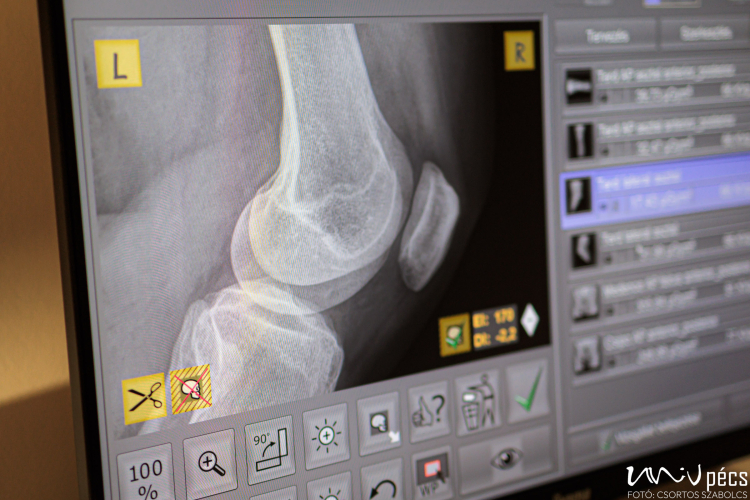

A C400-as röntgenberendezés mennyezetre szerelt, teljesen motorizált eszközpozicionálással rendelkezik, amely lehetővé teszi a gyors és precíz vizsgálatokat, beépített ütésgátló érzékelői pedig a biztonságos működést garantálják. A rendszer egyetlen konzolon keresztül, zökkenőmentes és hatékony munkafolyamatot biztosít.

A digitális képalkotás és az utólagos képfeldolgozási technológiák révén a berendezés kiemelkedően részletgazdag és nagy felbontású képeket készít, ami segíti a pontos diagnózis gyors felállítását, és így a hatékonyabb betegellátást.

A berendezés fejlett sugárdózis-tervező rendszere és az automatikus képfeldolgozási technológiák minimális sugárterhelést biztosítanak a betegek számára, miközben a képminőség továbbra is kiváló marad.